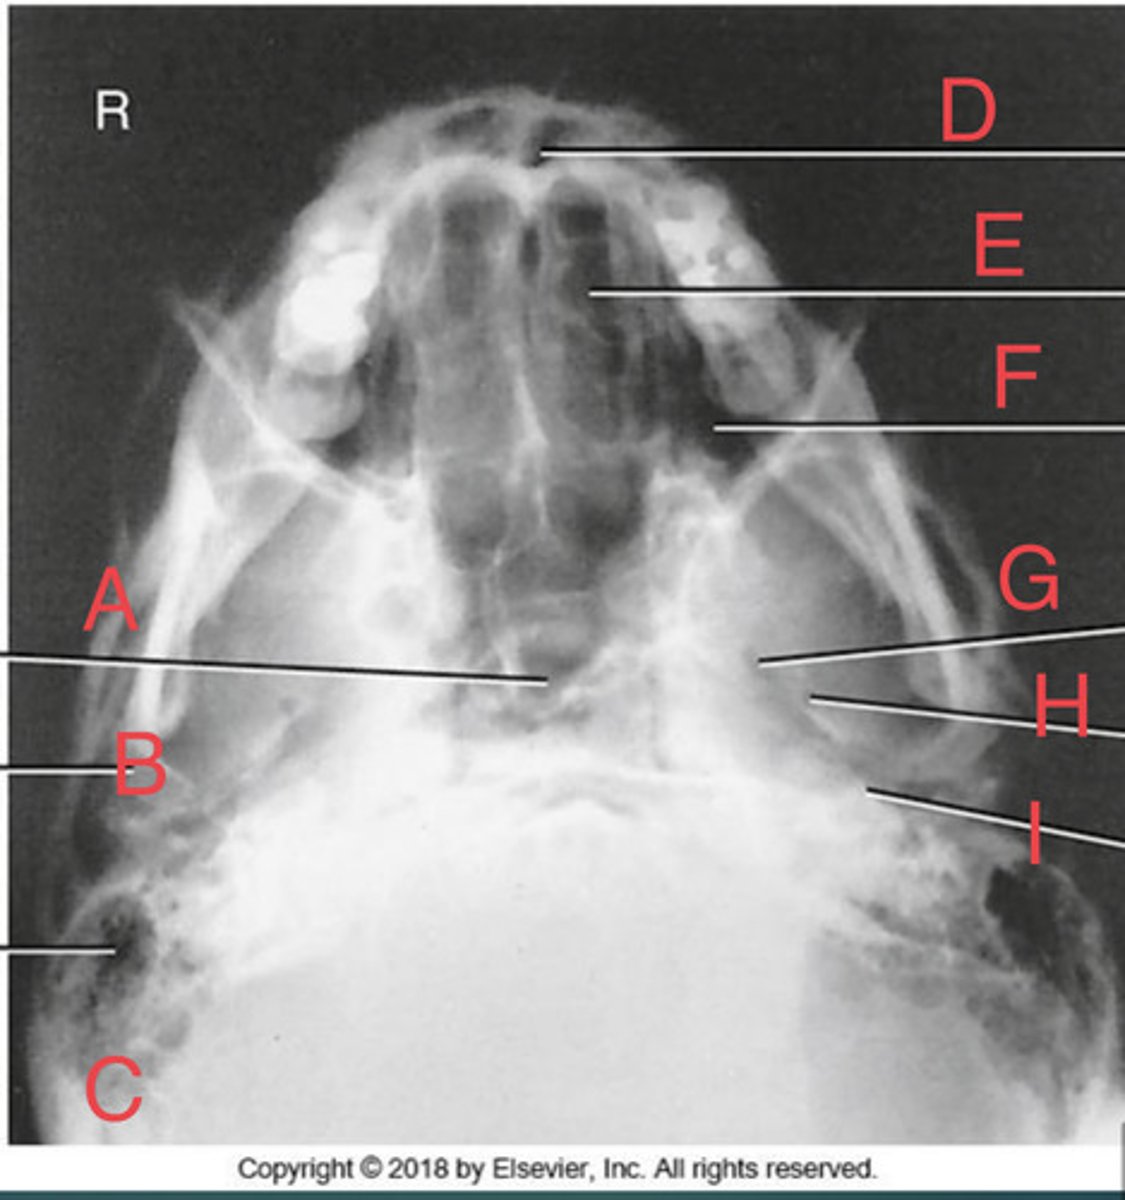

SMV sinuses

What position?

Sphenoid sinus of sphenoid bone

A.

R mandibular condyle of mandible

B.

R Mastoid air cells of temporal bone

C.

Nasal fossa

D.

L. Ethmoid sinus of ethmoid bone

E.

L maxillary sinus of maxilla

F.

L foramen ovale of sphenoid bone

G.

foramen spinosum of sphenoid bone

H.